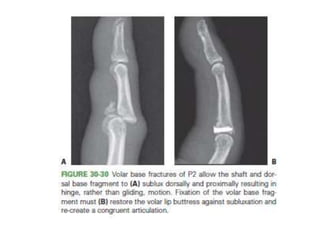

• Volar Base Fractures

– CRIF /ORIF

• #52 When the volar fragment constitutes greater than around 40% of the articular surface, this fragment carries the majority of the proper collateral ligament insertion in addition to the accessory ligament and volar plate insertions. The dorsal fragment and remainder of P2 will thus sublux proximally and dorsally with displacement being driven by the pull of the FDS and the central slip.